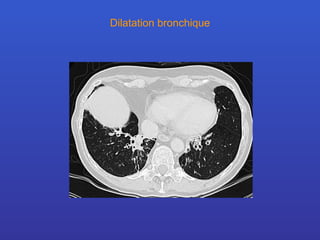

Dilatation bronchique